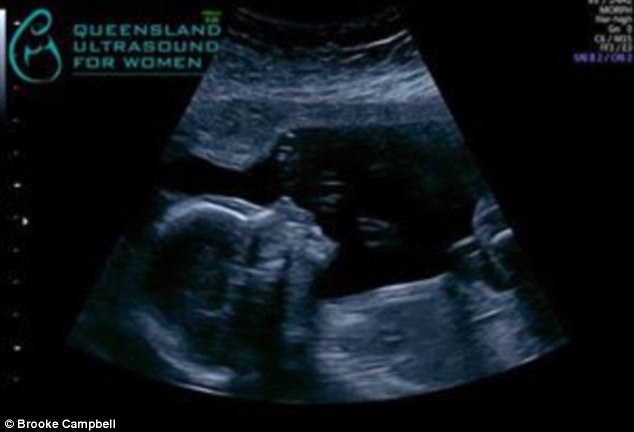

▼這名27歲的媽媽布魯克(Brooke Campbell)原本已經育有一子,在知道自己即將誕下的也是兒子之後,還已經為這名未來的家庭成員取好了名字,叫做達西(Darcy)。

▼可是在8月28日時,布魯克突然大量失血超過1.7公升,緊急送醫之後發現原來寶寶因為胎盤剝離引起缺氧,在送達醫院時已經在腹中夭折了。